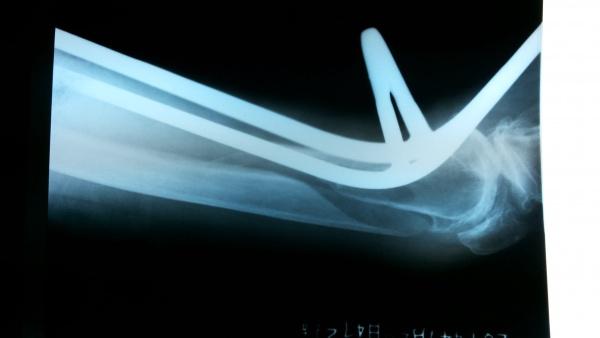

诊疗过程:入院给予:屈膝位胫骨结节持续骨牵引,消肿止痛,完善相关检查。今日复查床旁X片后家属要求手术。

牵引后床旁侧位片

牵引后床旁正位片